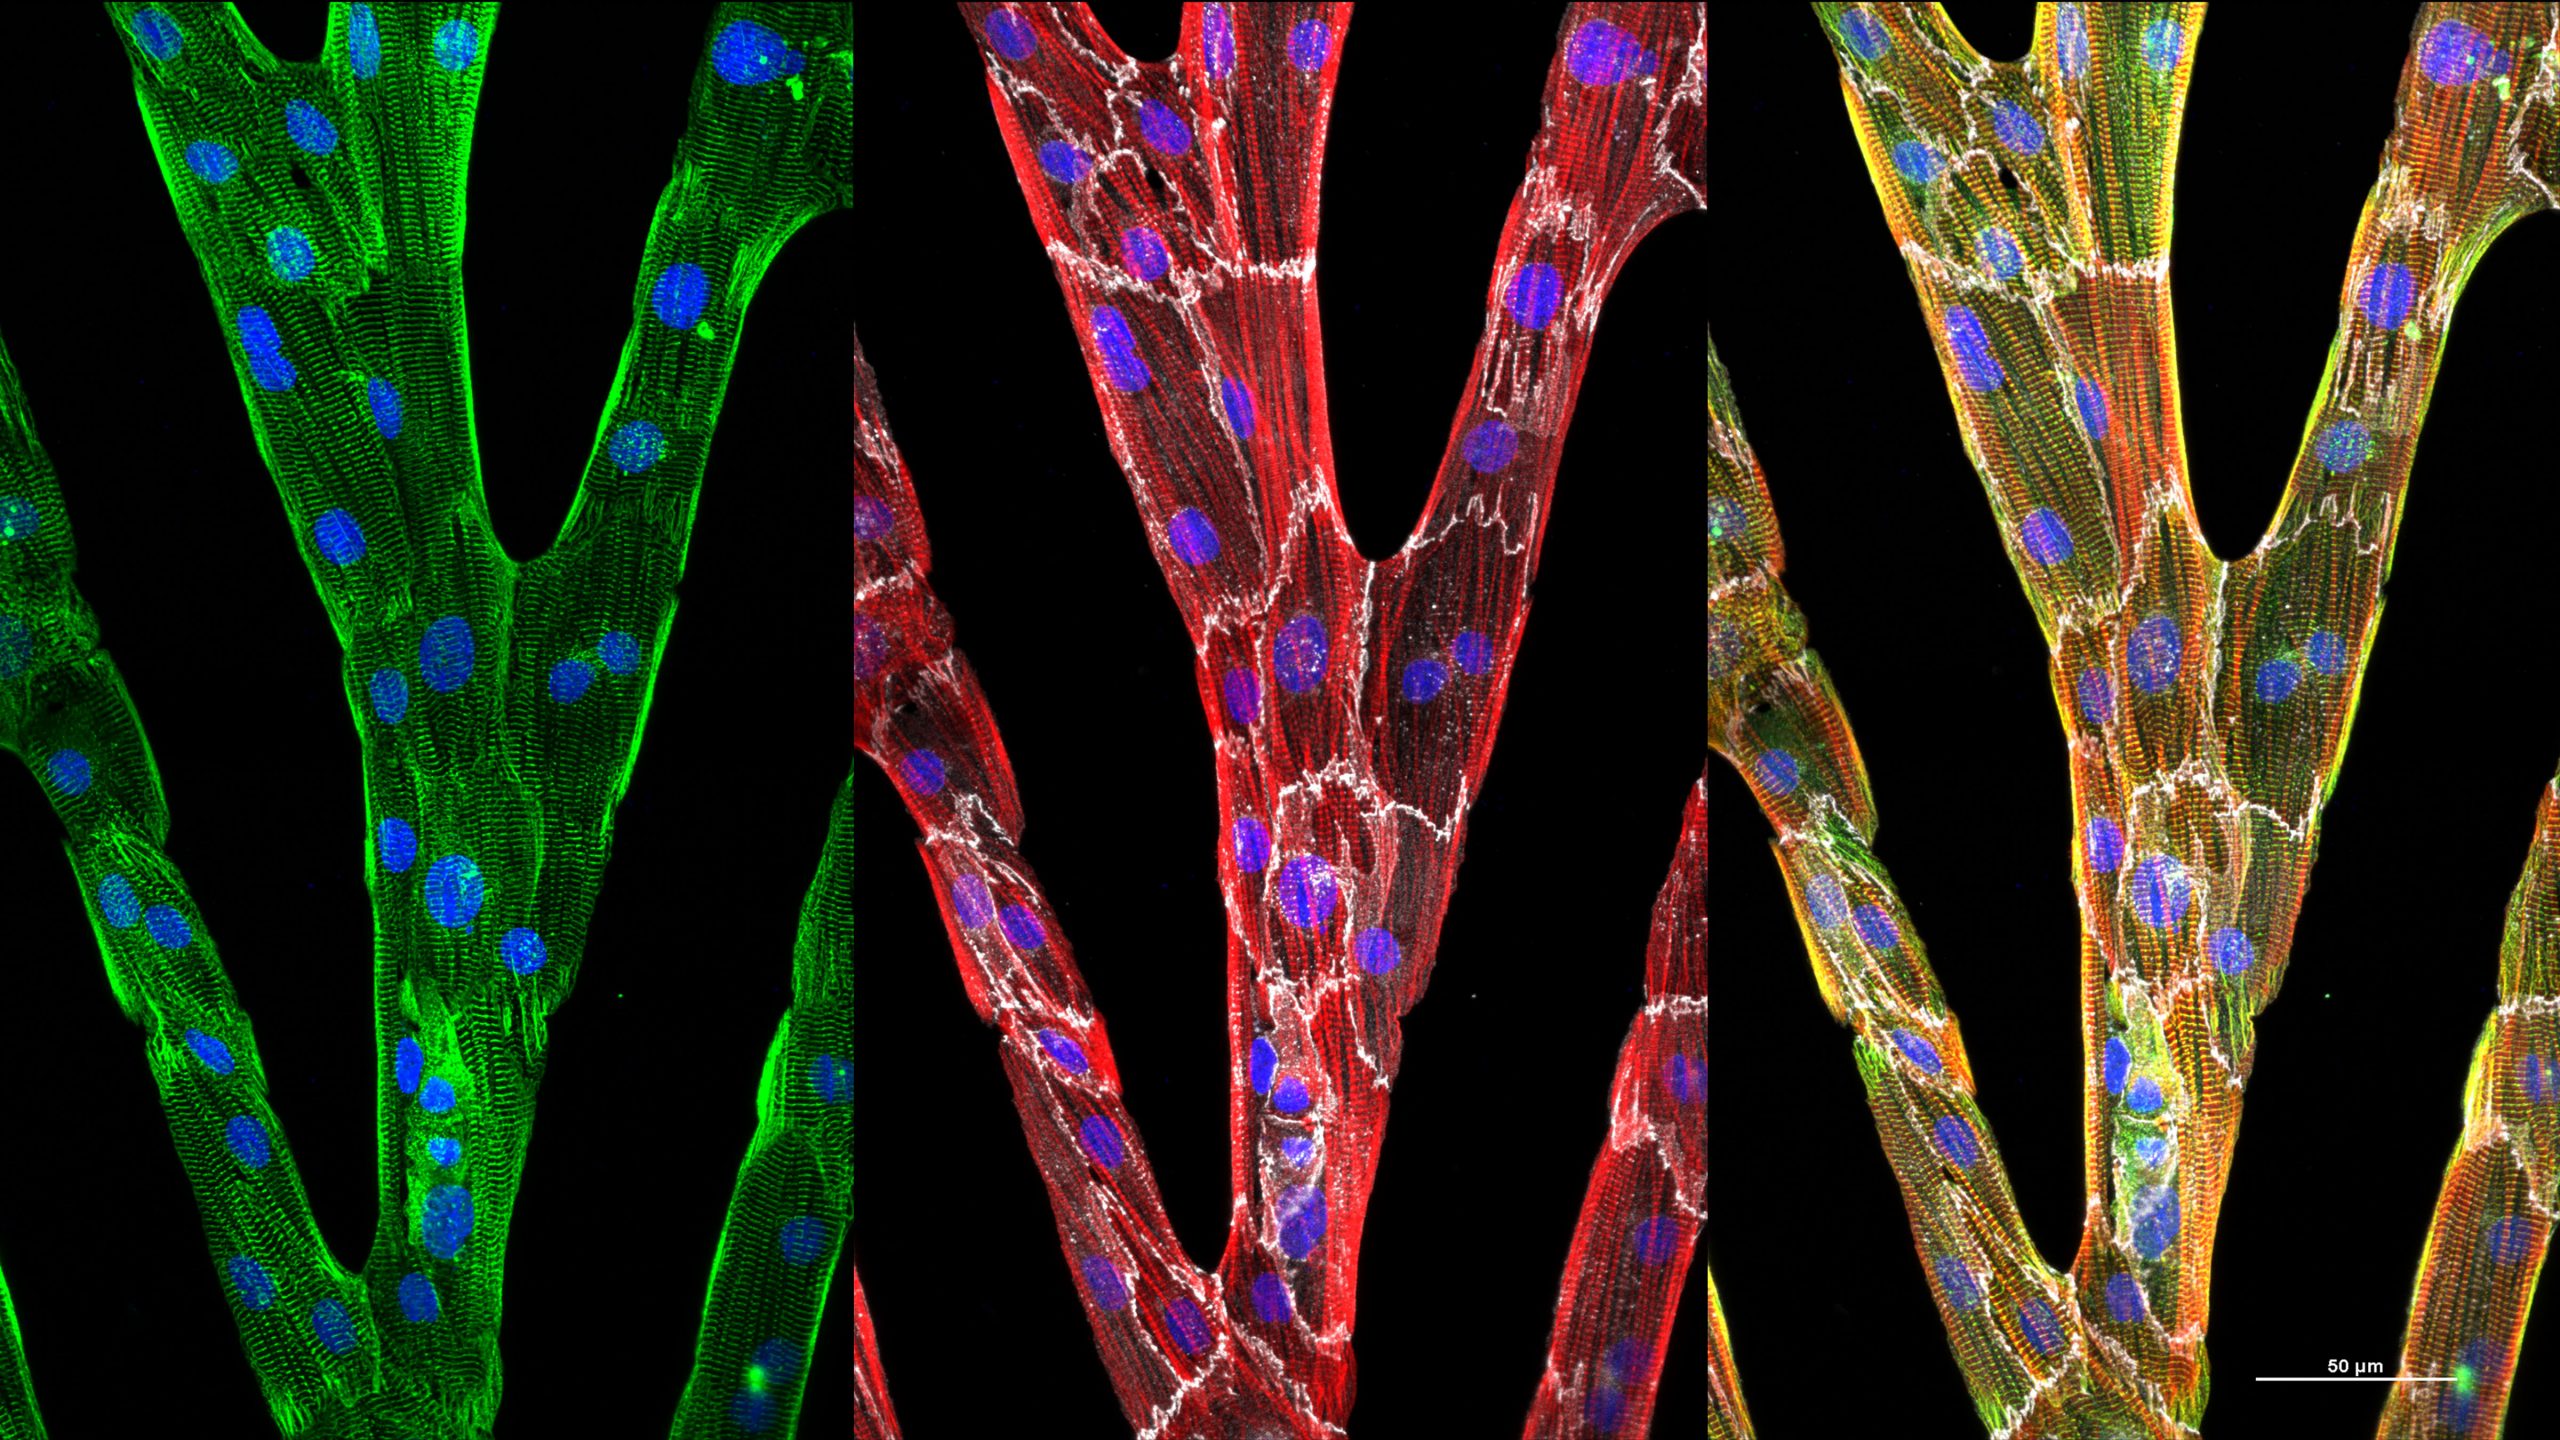

Human Induced Pluripotent Stem Cell derived Heart Cells cardiom UIC

A Heartbeat In A Dish Growing Specialized Heart Cells